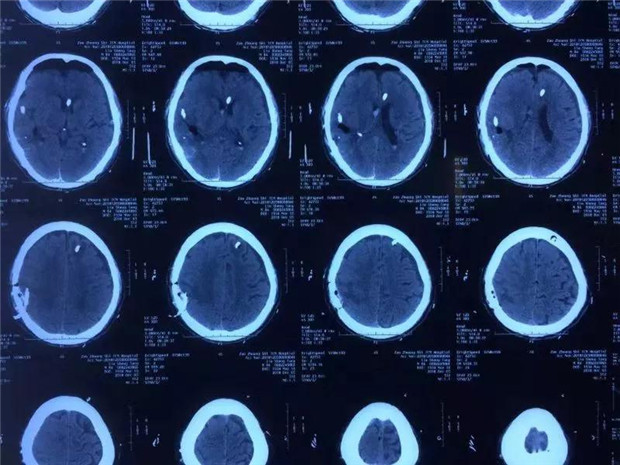

考虑病人高龄,手术采取了具有微侵袭代表的内镜技术,通过一元硬币大小的骨孔,在镜下操作,彻底的清除了血肿,解除了脑受压,并找到了责任血管止住了出血。老人术后逐渐苏醒,肢体可正常活动,脑疝症状消失,颅脑CT正常,恢复部分语言功能。

患者术后脑CT